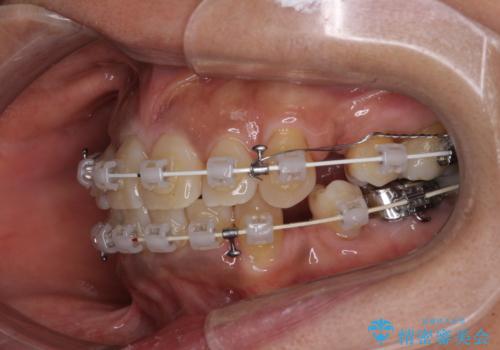

- 審美装置

- 2年4ヶ月

- 八重歯やクロスバイトを気にして来院された患者様です。

口元の突出感はありませんでしたが、デコボコが強く、非抜歯矯正とすると出っ歯仕上がりとなる可能性があったため、上下左右の第一小臼歯4本を抜歯し、ワイヤー装置にて矯正治療を行うこととしました。